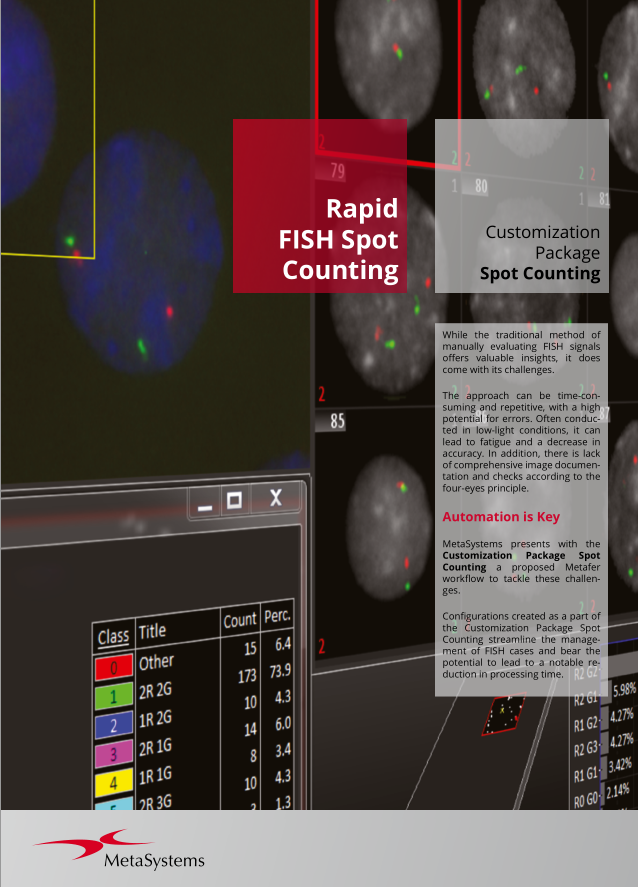

Metafer’s classifier system brings smart automation to object recognition. Combining advanced algorithms with user-defined criteria, it lets users categorize samples quickly while keeping workflows consistent and reliable. With integrated Deep Neural Networks (DNN), Metafer handles diverse sample types with precision, flexibility, and intelligence.

Customization Packages

To help you get the most out of this modular workflow approach, our Customization Packages offer more than a standard setup: they deliver a comprehensive service for configuring Metafer precisely to your task. Drawing on extensive experience from similar installations, our application specialists work closely with your team to define and refine the optimal workflow for your laboratory. This expert support accelerates the path from installation to user validation and routine operation, ensuring a faster, more confident start.

MetaSystems offers Customization Packages for application workflows that have been successfully implemented for customer labs using standard Metafer platform functionality. It is expected that they can be implemented for other customer labs using similar workflows and slide preparation procedures. If a Customization Package is purchased, MetaSystems product specialists will – based on their experience from other similar application cases - support the customer lab in adapting the Metafer software configuration to their needs. The performance of the solution will depend on the quality of the customer slides and the expertise of the users, MetaSystems cannot specify or guarantee any performance parameters. The validation of the solution for clinical use is the sole responsibility of the customer lab.